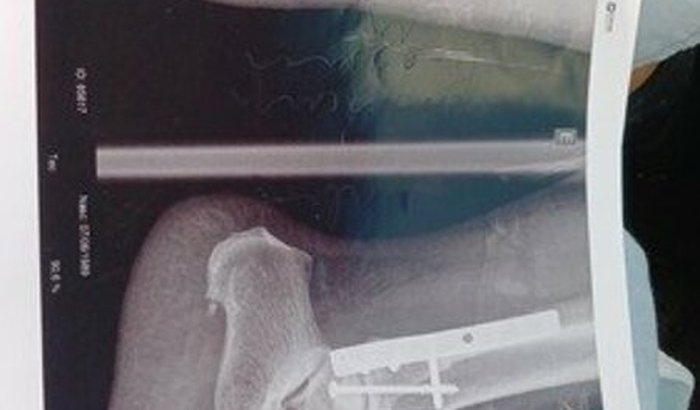

eu sou Fernanda sofri um acidente  de moto quebrei  o tornozelo  dos dois lados precisei passar por uma cirurgia  e vou ter operar  novamente  preciso  ajuda pra pagar as medicação  o aluguel  da cadeira  do andador e moleta  pois eu trabal ver tudo

eu sou Fernanda sofri um acidente  de moto quebrei  o tornozelo  dos dois lados precisei passar por uma cirurgia  e vou ter operar  novamente  preciso  ajuda pra pagar as medicação  o aluguel  da cadeira  do andador e moleta  pois eu trabalhava por dia  não  tenho renda as contas se acúmulos pago aluguel da minha  casa Tb quem puder ajudaragrade eternamente...